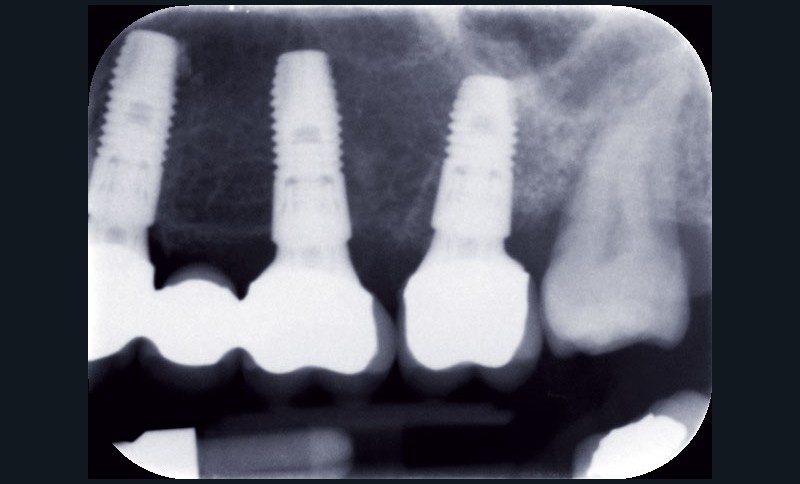

Au maxillaire, 3 implants Astra Tech Implant EV (Dentsply) sont posés en un temps chirurgical. Une empreinte pick-up sera réalisée après 4 mois de cicatrisation.